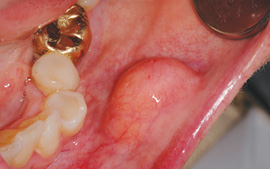

One such entity that is often perplexing to the clinician is the lipoma. (see Figure 1) It is one of the most common total body tumors, yet it is also a rare benign neoplasm not often found intraorally. In order of occurrence when found intraorally, these growths may occur on the buccal mucosa (because of the abundant fatty tissue), the tongue, the floor of the mouth, buccal sulcus, palate, lips, and gingiva (Kumaraswamy et al.2009). They have also been found in the oral pharyngeal area and may interfere with swallowing. This is another excellent reason to critically examine the tonsillar and pharyngeal areas since tonsillar cancer is a prime concern as well.

Lipomas are slow growing, painless, soft, smooth-surfaced, palpable masses, and are noted as having a yellow hue. They are unlike the fibroma, which does not normally present with a yellow-tinged surface and presents a more firm and flesh-toned appearance.

Lipomas are usually discovered by the dental practitioner unless they become large enough to be detected by the patient. Eyewear and illumination give dental professionals an edge on detecting small growths. Most are discovered in a less than 3 cm diameter size, but large lipomas have been documented as well and may exceed 11 cm as reported by Chidzonga, et al. 2006, who documented a gigantic tongue lipoma. When they are left untreated and continue to grow, larger lipomas occur. In a retrospective study of 207 patients with intraoral lipomas conducted by Taira, et al. 2012, the most frequent size was reported to be 10-19 mm with a finding of 57.5% males and 42.6% females.

One to four percent of lipomas occur intraorally and they may be confused with the fibroma when found in some locations of the mouth -- especially in areas where friction may occur. A combination of a fibroma and lipoma is documented and is referred to as the fibrolipoma. The fibrolipoma has characteristics of both fibrous connective tissue and adipose tissue when viewed microscopically. Although the lipoma is benign, the malignant counterpart to the lipoma is the liposarcoma. The need to confirm that the entity is truly benign is crucial for a definite diagnosis.